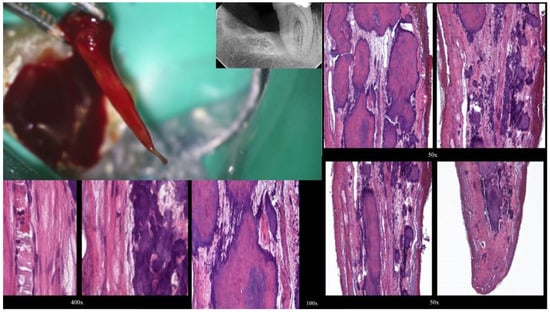

Figure 4.

Removal of a pulp stone from a second mandibular molar suffering from irreversible pulpitis. Micro-ct evaluation of the external and internal structure of the pulp stone. Notice that the structure of the pulp stone is not solid, presenting an internal network of unmineralized tissue. The clinical significance is that the pulp stones can be dissected in smaller pieces and removed (clinical, radiographic, and micro-CT images courtesy of Dr. Chaniotis Antonis).

Figure 5.

The free pulp stone’s histology shows distinct calcified nodules growing around a network of unmineralized extracellular matrix material and capillary vessels (hematoxylin–eosin staining) (histological images courtesy of Dr. Chaniotis Antonis).